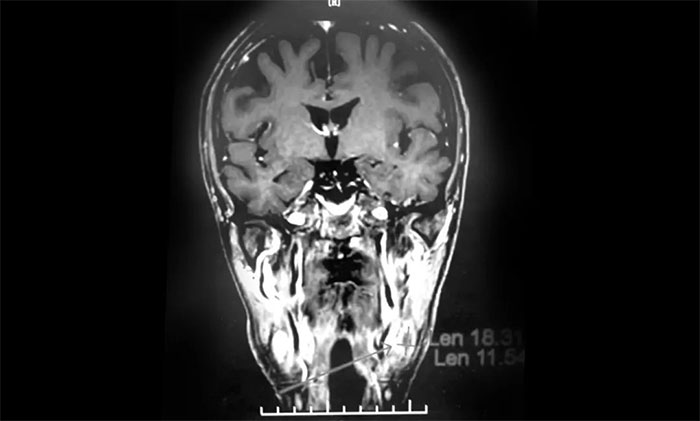

经MDT多学科会诊评估,制定以放疗为主的同步放化疗方案。治疗后复查MRI,患者左侧鼻咽部实性占位较前治疗明显减小;原左侧下颌腺区、咽旁肿大淋巴结已基本吸收好转,左颈部肿大淋巴结较前明显缩小。

▲ 放疗后复查MRI,肿瘤占位较前明显减小